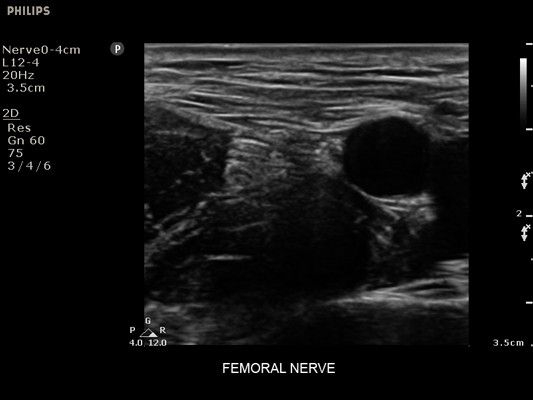

• Усиленная визуализация иглы без потери качества изображения окружающих тканей

• Метки центральной линии на датчиках L12-4 и C6-2 для упрощения внеплоскостной навигации

• Диагностика нервов

• Линейный УЗИ датчик Philips L12-4